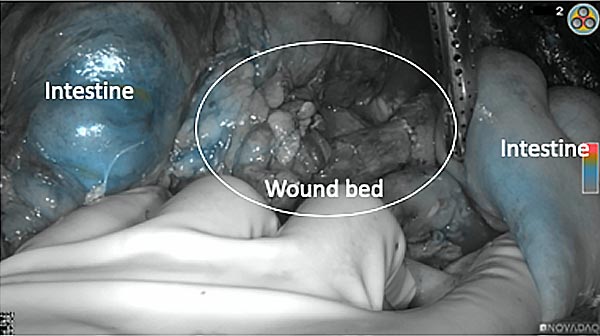

Intraoperative imaging panitumumab-IRDye800 (fluorescence)

Primary tumor prior to resection

Wound bed post re-resection of tumor

Fluorescence imaging of the tumor was performed prior to resection and after resection to “check” the wound bed. In the upper row the tumor is clearly visible with fluorescence and in the bottom row you can see that the wound bed is empty – there is no suspicious fluorescence left. The middle column of tiles show the fluorescence signal in black and white where the “white” represents the tumor and the black the background (= no fluorescence signal). The right column of tiles shows the overlay of the brightfield photo (in greyscale) and the fluorescence (red-yellow-blue heatmap). This image provides anatomical context to the surgeon – the surgeon can see where is the fluorescence located with regard to the tumor area.